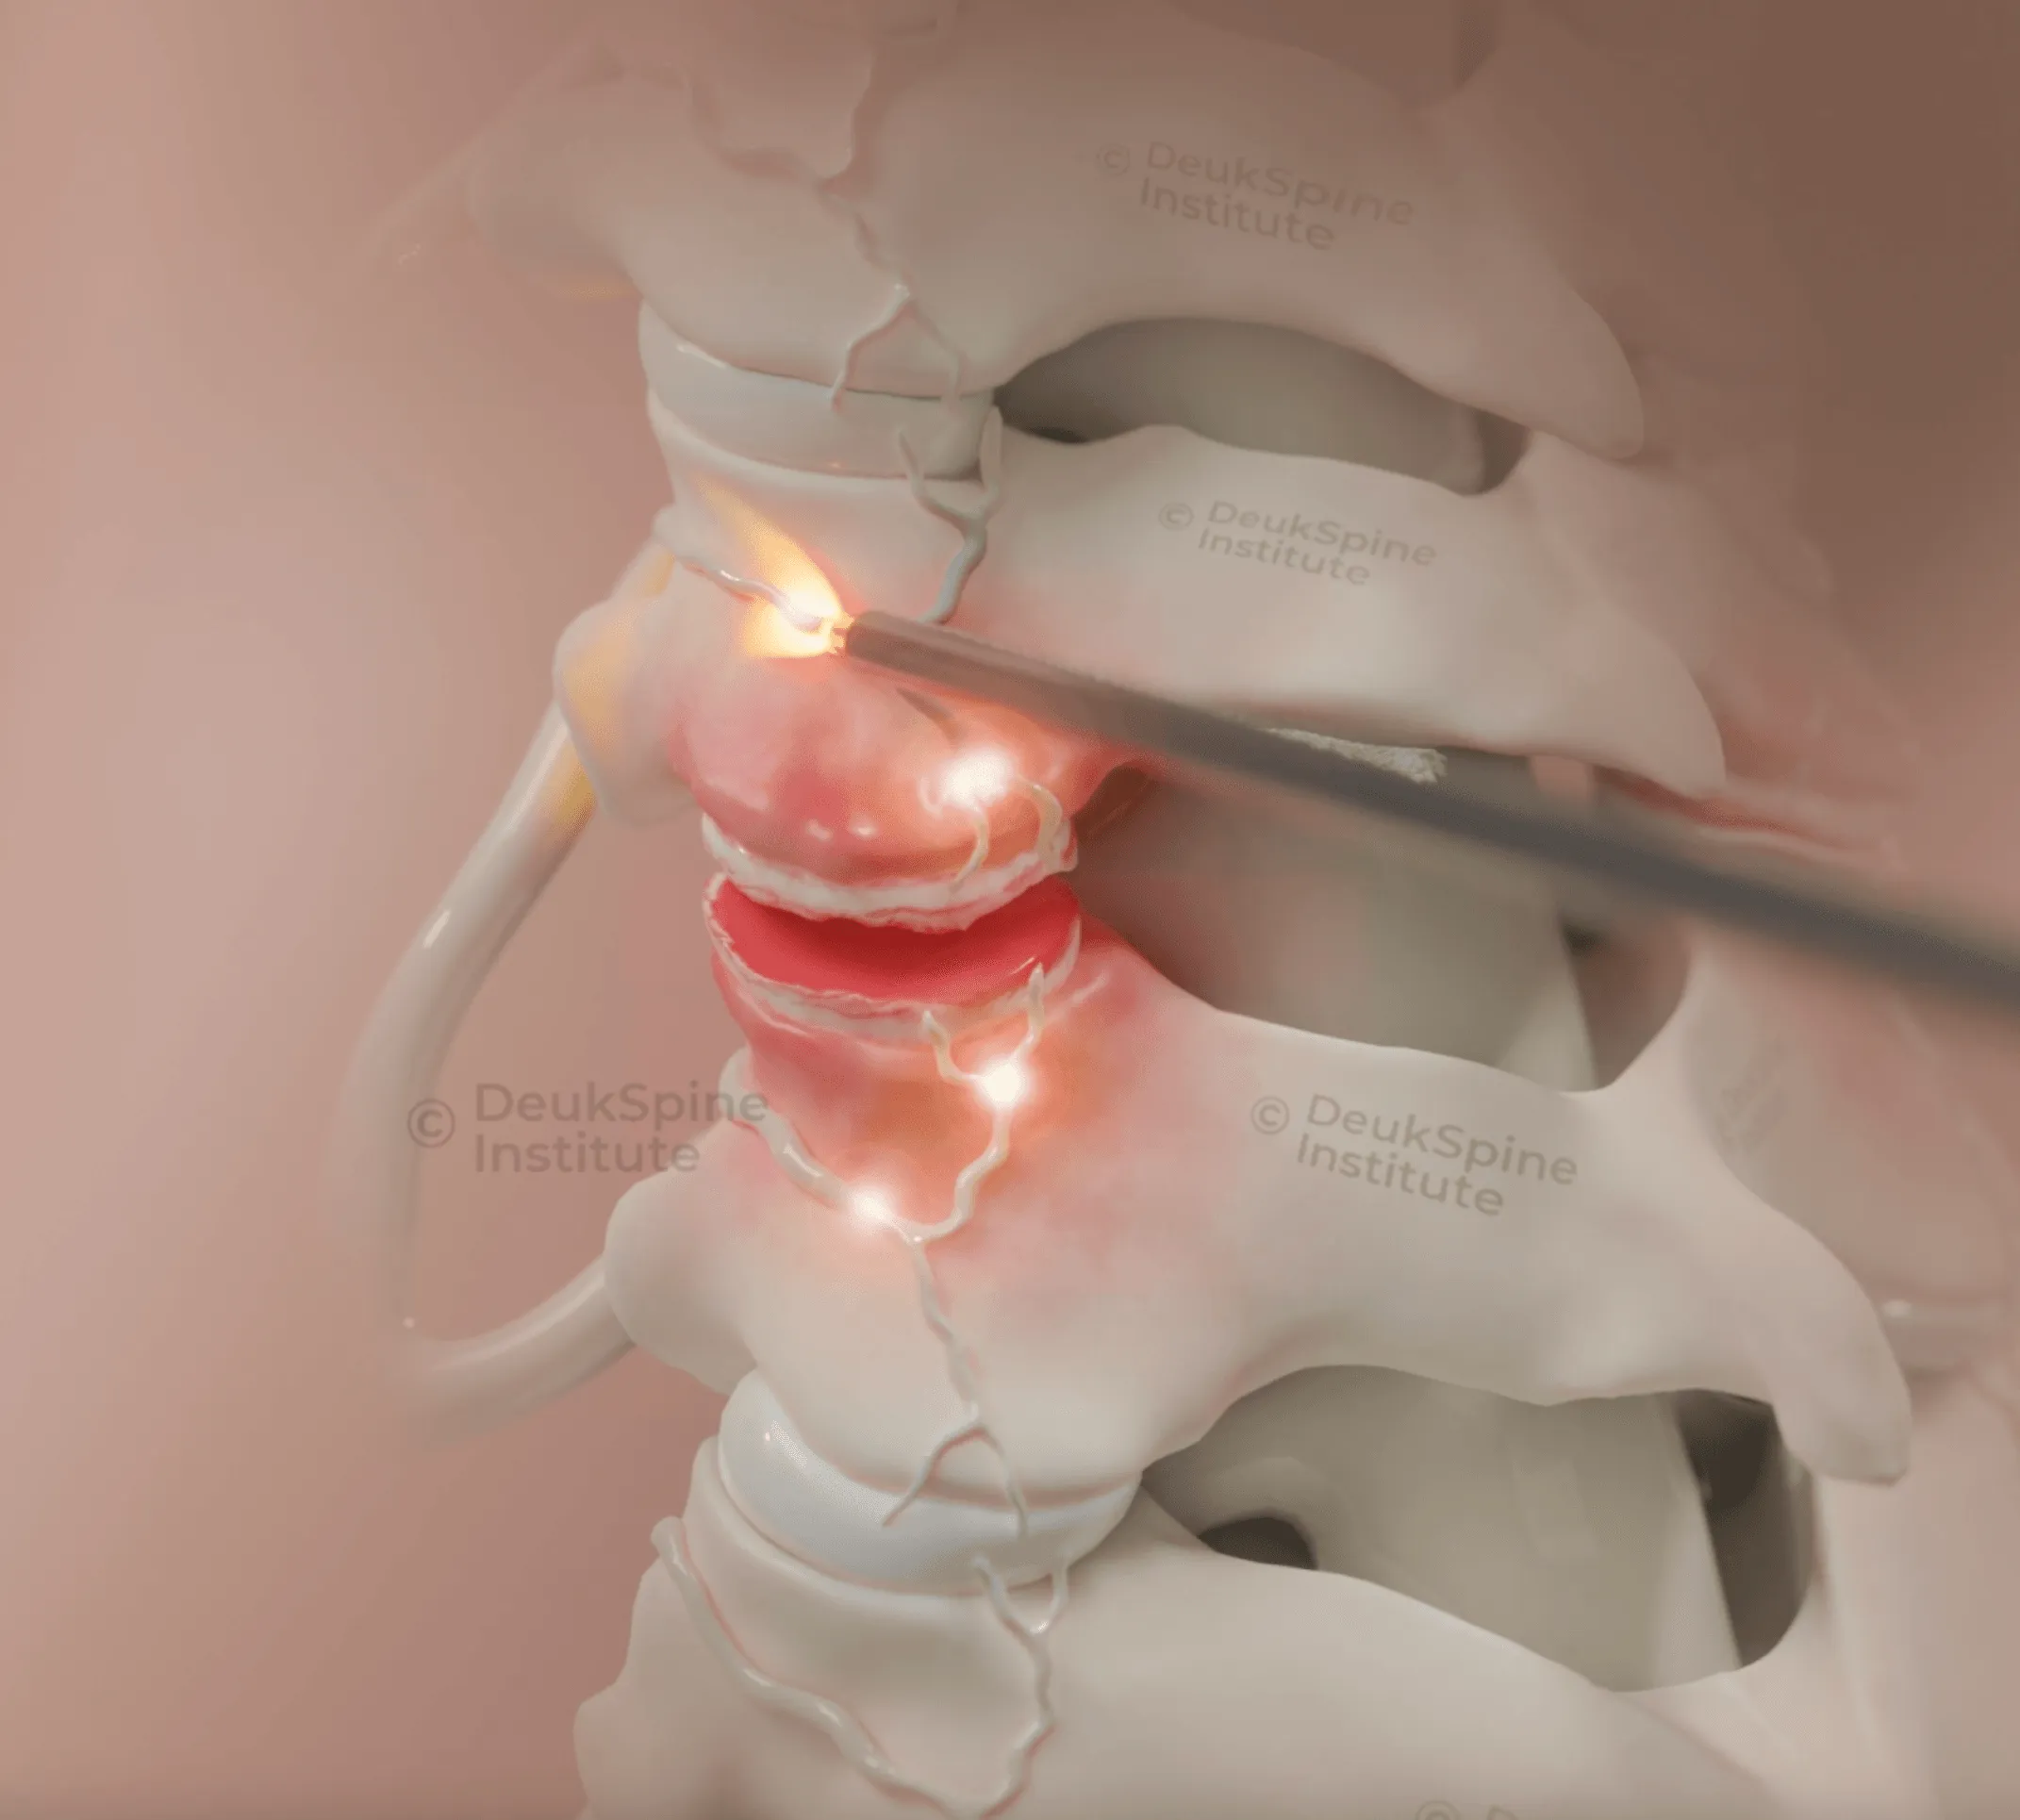

Your spinal discs have a tough outer layer (annulus fibrosus) surrounding a soft inner nucleus pulposus. When the disc degenerates or experiences injury, the annulus develops tears, most commonly in the back of the disc (posterior annular tear). Nucleus pulposus material from inside the disc can herniate through this tear.

The herniated material and the damaged tissue surrounding the posterior annular tear trigger an inflammatory response. This inflammation, combined with mechanical stress on pain-sensitive structures in the outer annulus and posterior longitudinal ligament, generates your pain signals. Small pain nerve fibers can grow into the damaged and inflamed area, potentially intensifying the pain over time. This is why disc pain often worsens gradually rather than improving. The inflammatory process can become persistent.

Disc injury with annular tear: Treatment must address the inflammatory tissue around the tear and remove any herniated material compressing the nerve. The Deuk Laser Disc Repair® is a proprietary procedure that removes inflammatory tissue, performs an annular debridement, and allows the disc to heal naturally. In our clinical experience with over 2,700 Deuk Laser Disc Repair® procedures, patients report an average of 99% pain relief for treated pain sources, with a complication rate of only 0.01%.